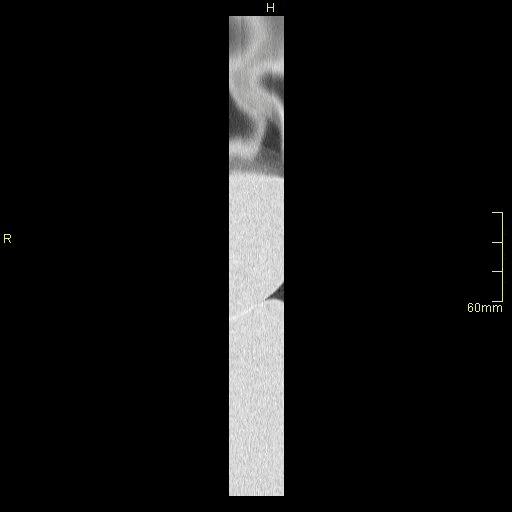

HRCT - Coronal Prone Inspiration (Lung Window)

HRCT - Coronal Supine Inspiration (Lung Window)

HRCT - Coronal Supine Expiration (Lung Window)